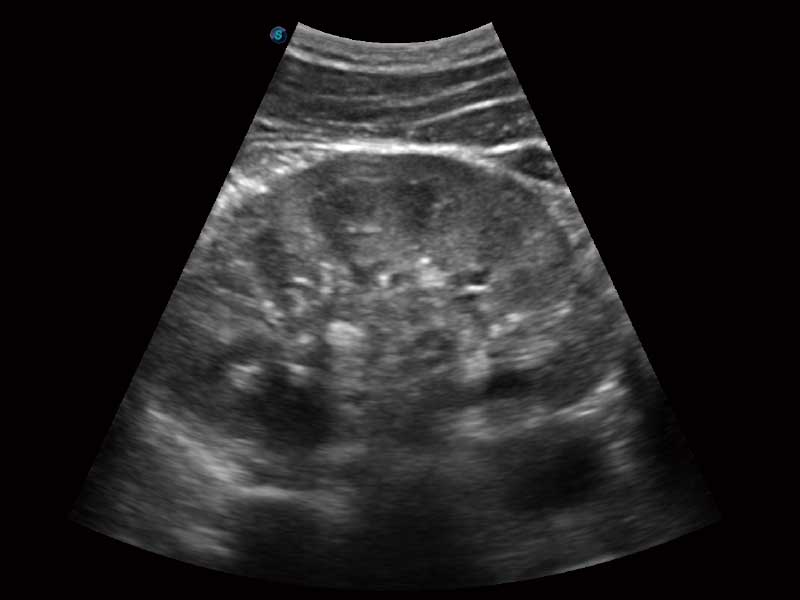

E2便携式彩色多普勒超声诊断系统采用专业的超声技术平台、高度集成化的硬件模块和结构设计、简便的操作流程、多探头接口设计,兼顾了优质图像、轻便机身以及台便两用的临床使用需求。

μ-Scan微米成像、空间复合成像、高分辨率血流成像。